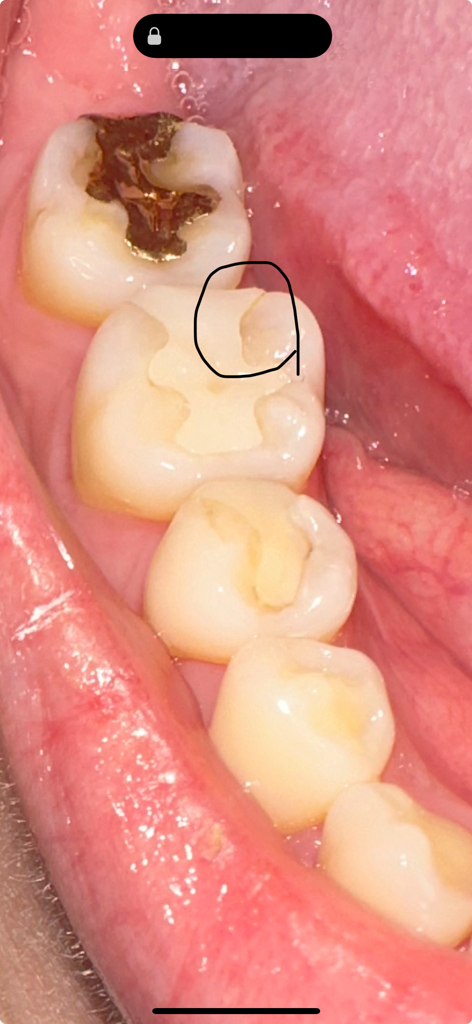

보철물과 치아 틈이 생겼어요 크게 아프거나 불편한건 없지만 나중에 더 안좋아질수도있으니 무조건 보철물 교체를 해야할까요? ㅠㅠ 치과 방문은 금요일에 할 예정입니다.. 혹시 충치가 눈으로만 봐도 보이나요? ㅠㅠ

• 2번 째 사진